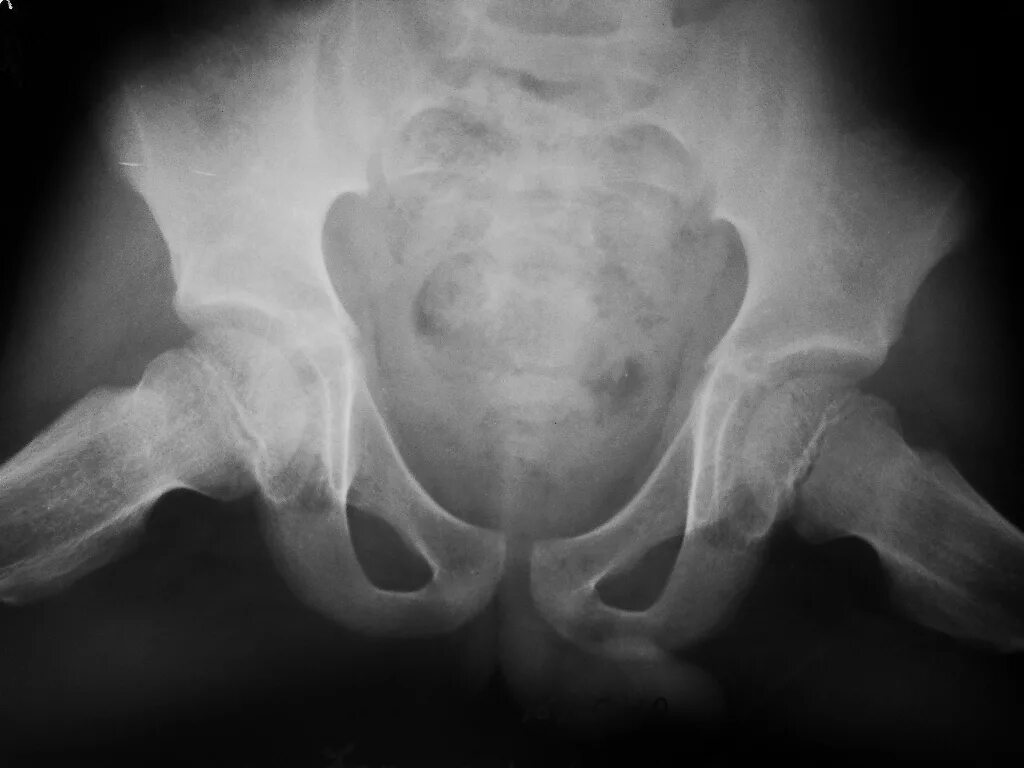

Рентген тазобедренный в двух проекциях